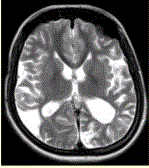

问题 女性,22岁。癫痫发作及智力异常。MRI显示见下图。 有关该病的描述正确的是(提示MRA所示如图。)

选项 A.双侧颈内动脉及其分支部分闭塞 B.双侧大脑后动脉狭窄、部分闭塞 C.颅底可见大量侧支循环形成 D.血管未见明显异常 E.双侧椎动脉显示清晰 F.双侧颈内动脉显示清晰

答案 ABC